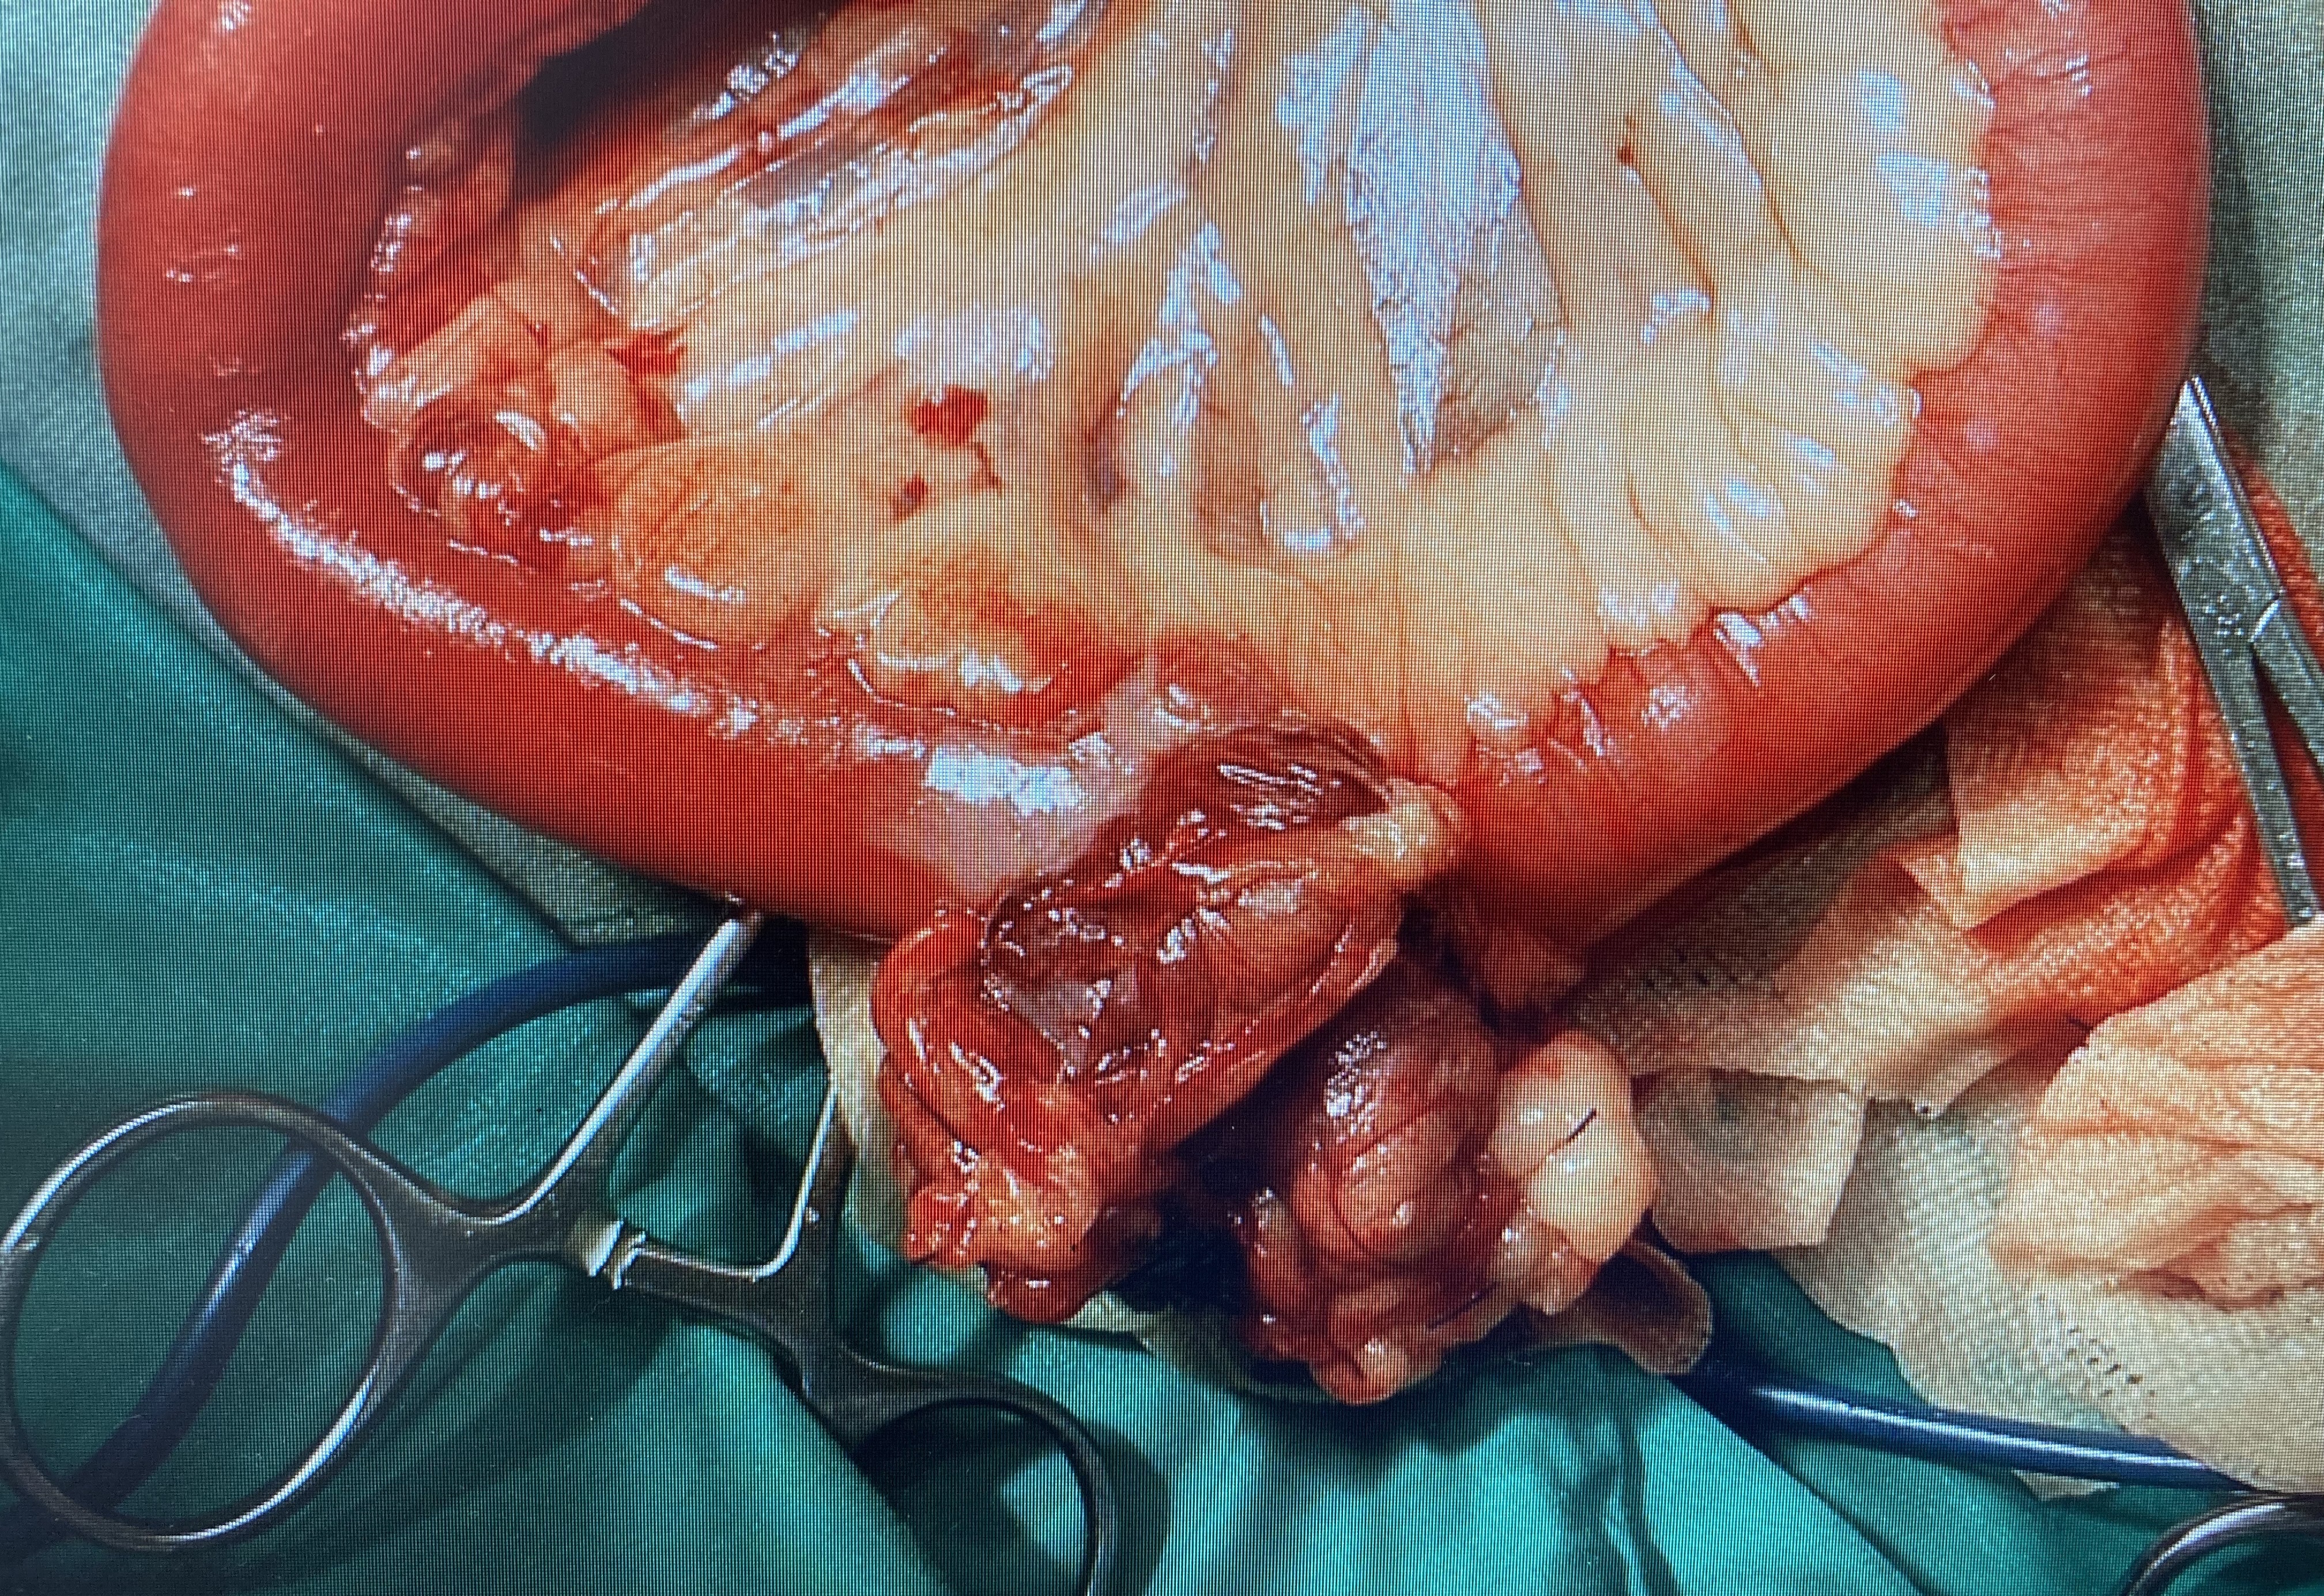

小腸内の閉塞異物は腸切開手術で取り出すことがあります。チワワの若いこで嘔吐が続く事例でしたが、腹部エコー検査で腸内異物による腸閉塞が疑われたため、手術で取り出しています。殻付きの銀杏かピスタチオと考えられる異物でした。1cm程度の種子など異物は消化されず、小腸で閉塞することが多く大変危険です。他に桃の種、梅干しの種などが腸閉塞をよく起こします。